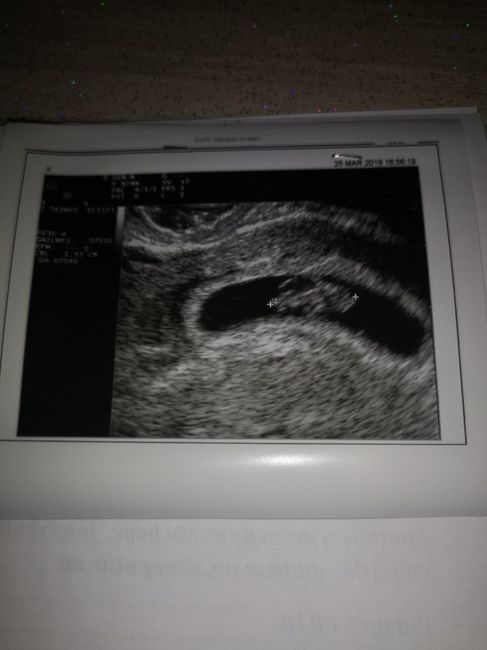

Ciao ragazze oggi 8 settimane, ho fatto la prima eco ... sono un po’ perplessa per la forma della camera ma la gine m ha detto che va bene (io glielo ho chiesto più volte perché a me nn sembra molto normale). Voi che dite ? Le vostre come erano? Vi...